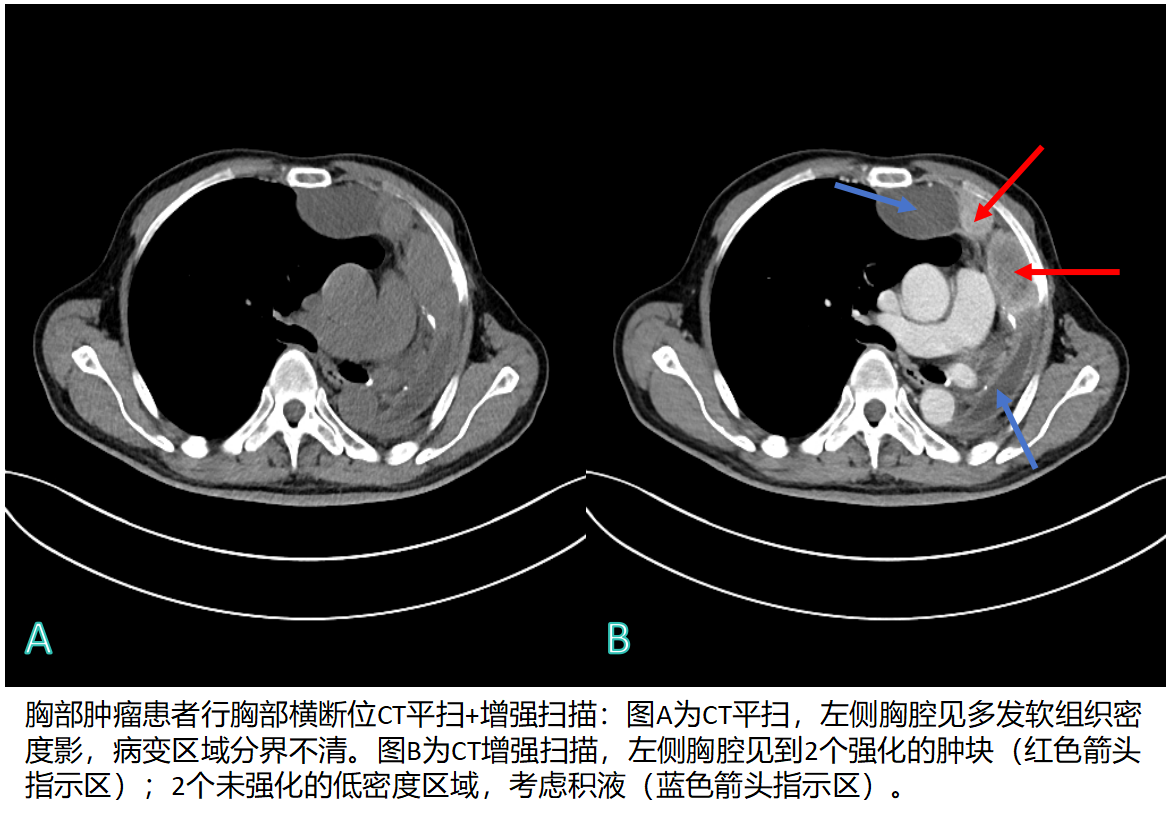

3126217f4856f202872ff4123ff3f037.png

db76a7ade7c40434d369b12d81df1471.png